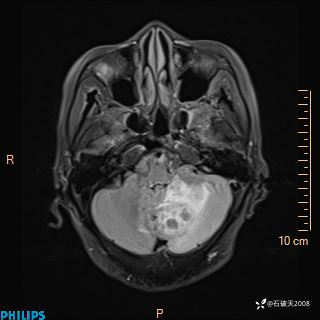

女 86岁 主 诉:乏力1月

现病史:患者1月前活动出现双下肢乏力,无头晕、头痛、恶心、呕吐、肢体活动不利,休息后缓解,间断断发作,症状进行性加重,在家口服药物治疗(具体不详),效差,为进一步诊治,来我院,门诊按“乏力”收住我科,患者自发病以来,神志清,精神稍差,饮食睡眠欠佳,大小便正常,体重未见明显改变。

DWI